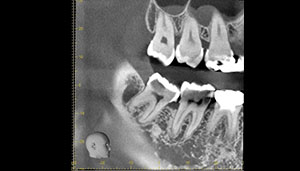

CT

CTで親知らずと神経(下歯槽管)の位置を確認しました。

親知らずと神経は一定の距離があり、麻痺などのリスクがほとんどないと判断できます。